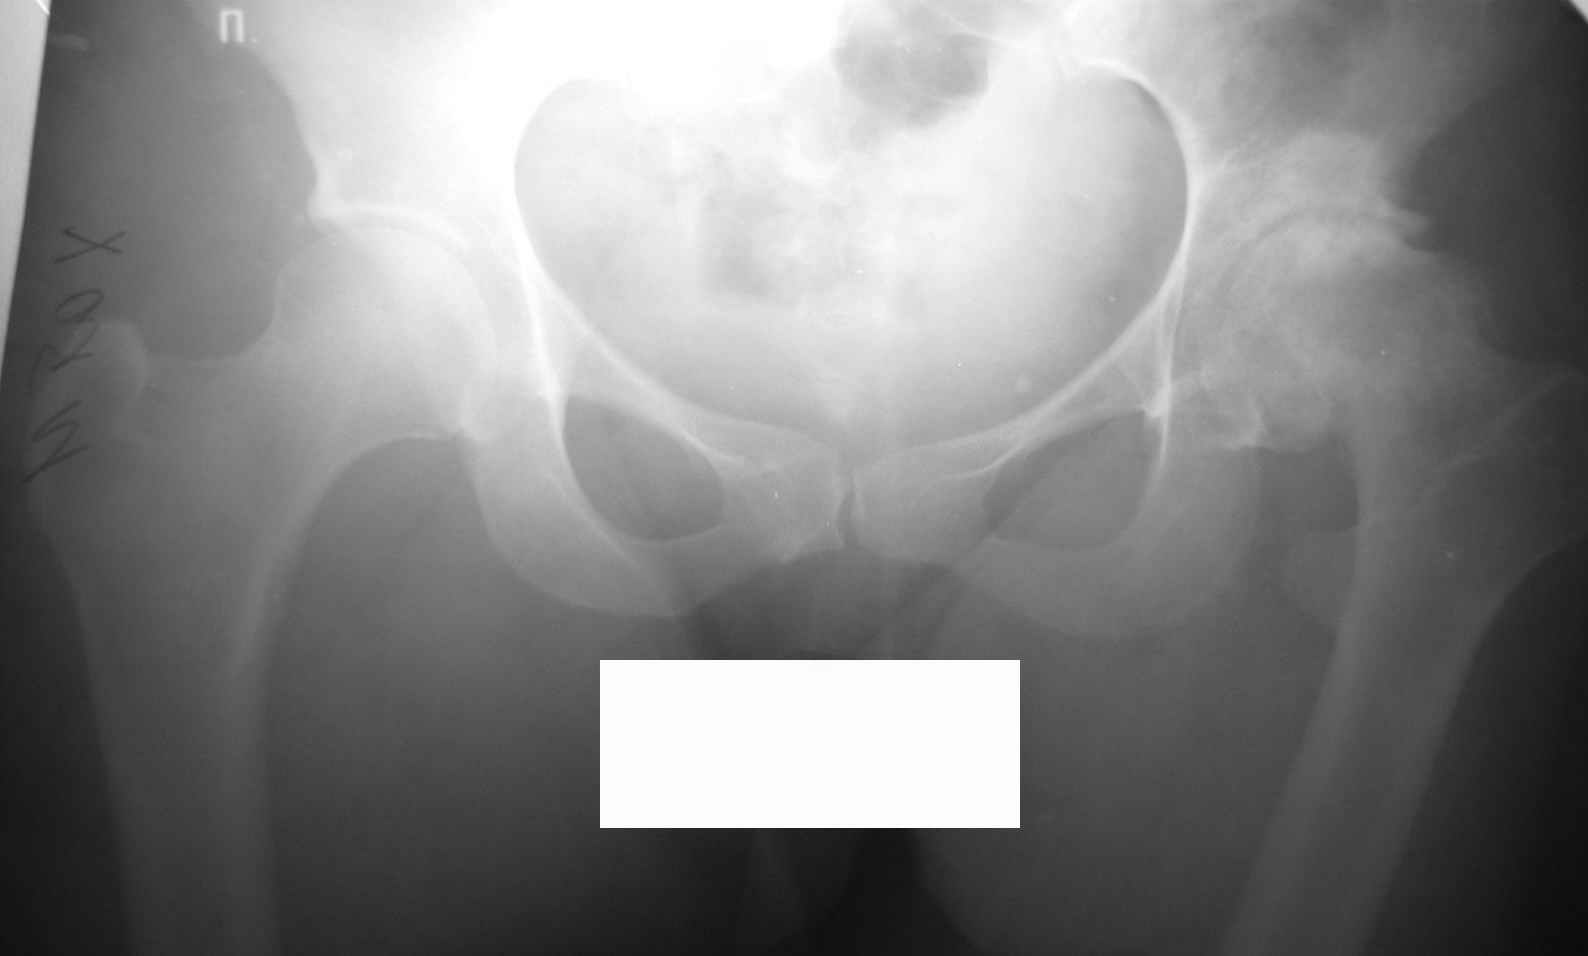

Уважаемые коллеги, во вложении р-граммы 24-летней женщины. Обратилась первично.

Жалобы на боли, ограничение движений, хромоту. Болеет с 14 лет. С её слов, перенесла болезнь Пертеса. Документов нет. Обьективно: выраженнаяприводяще-сгибательная-ротационная контрактура, функциональное укорочение - 5см.Вопросы:-какая система, на ваш взгляд, наиболее оптимальна для протезтрования?-возможно-ли выполнить протезирование в один этап,восстановив длину и функцию конечности?Спасибо.Ринат. г.Уфа

Судя по седловидной деформации головки бедренной кости можно предположить, что больная перенесла болезнь Пертеса.

Извините, Анатолий, головка не выглядит потерянной, укорочение 5 см из-за порочного положения. Подход у молодой женщины я бы выбрал в зависимости от мобильности сустава.

На ригидном суставе межвертельная остеотомия для женщины мало привлекательна, но при гипомобильности, а тем более мобильности сустава вполне пригодна. И эффект от операции мы наблюдаем больше 10 лет и для последующего эндопротезирования трудности не велики, если остеотомию правильно спланировать и выполнить (проксимальный отдел бедра после остеотомии должен соответствовать нормальной анатомической геометрии). Привожу, что под рукой - Ртг 1997 ( даме 27 лет) и 2004 года. А моделей эндопротезов бесцементной фиксации для такой рентгеноантомической формы коксартроза действительно достаточно.

По представленным раздельным Рг граммам сложно судить о причине столь значительного укорочения, вполне вероятно что причина комплексная:

1 разрушение головки

2 разрушение впадины

3 поясничный сколиоз

При предоперационном планировании дифференцируют относительное укорочение (обусловлено перекосом таза, поясничным сколиозом) конечности и абсолютное - истинное (разрушение головки бедра и вертлужной впадины, приводящее к смещению центра ротации). В идеальных условиях целью эндопротезирования является восстановление уровня центра ротации. Приводящие контрактуры, поясничный сколиоз обычно вторичны деструктивным процессам в суставе и на уровень центра ротации, абсолютное укорочение конечности не влияют.

Поэтому и важно иметь правильно выполненную Рг таза целиком, а не из половинок и с помощью референс линий определить истинное укорочение и необходимую величину коррекции. После эндопротезирования сустава решается вопрос о необходимости аддукторотомии.

По моему мнению, у Вашей пациентки выявлены последствия эпифизеолаза (slipped capital femoral epiphysis).В данный момент у нее наблюдаются признаки коксита (laminar coxitis), что является наиболее тяжелым осложнением в таких случаях. Я не мог бы предложить другого метода лечения, кроме эндопротезирования сустава. Удлиннить бедро на 5 см. можно во время операции без особых затруднений с помощью тенотомий.